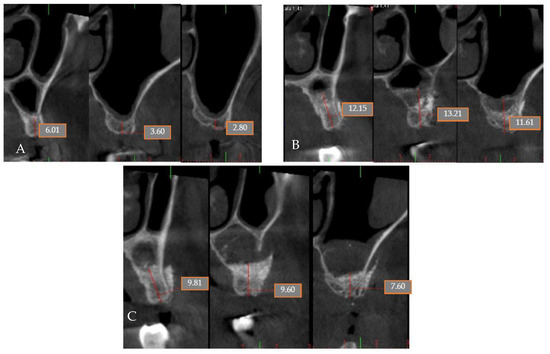

4.5. Patient No.5

4.6. Patient No.6

| 5 M 64 | NO [-] Sinus lift with lateral window | Yes [No] | G | No | G | No | No |

| 6 M 46 | NO [-] Sinus lift with lateral window | Yes [No] | G | No | G | No | No |